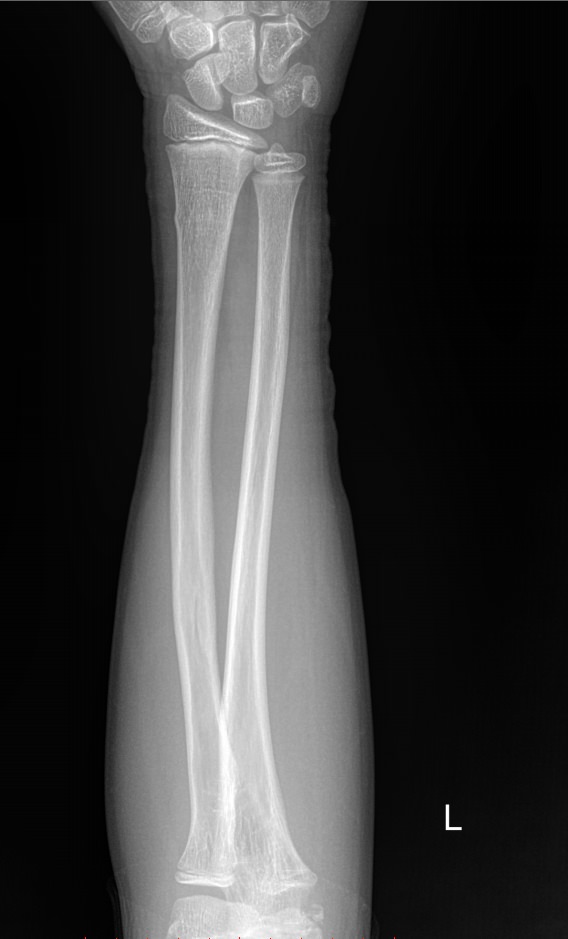

В предплечье входят 2 кости ― лучевая и локтевая. Вместе они соединяют кисть с плечом и обеспечивают движение и повороты руки. Переломы костей происходят в наиболее тонких местах ― ближе к суставам. Реже встречаются костные и мышечные патологии и онкология.

Обследование поврежденного или пораженного предплечья начинают с рентгенографии. Современное оборудование несет минимальное количество обучения и позволяет делать несколько снимков подряд, например, для контроля хирургического лечения. В снимок кроме собственно локтевой и лучевой кости попадают оба смежных сустава ― локтевой и лучезапястный. Также видны и мягкие ткани.

Что покажет рентген предплечья

• Костно-травматические изменения лучевой и локтевой костей;

• Патологические изменения в костной ткани;

• Состояние мягких тканей;

• Состояние прилежащих суставов, их заболевания и травмы;

• Новообразования и метастазы данной области.